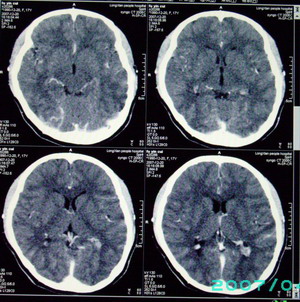

以下是引用九目段在2007-12-24 14:55:00的发言:[br]1,年轻女性[br]2,ct表现:左侧脑室三角区可见一不规则小明显强化的结节,中央见小低密度,侧脑室无扩张。[br]分析:[br]常见的有三种肿瘤好发三角区:[br]1,脉络丛乳头状瘤,好发于年轻者,明显强化,实性,分泌脑脊液,常伴有侧脑室扩大,肿瘤较小可以脑室扩大不明显,不能排除,但小结节尚不易形成坏死腔。[br]2,室管膜瘤,好发于儿童及青少年,明显强化,易坏死,大时伴脑室扩张。[br]3,脑膜瘤,明显强化,圆形,界请,无脑积水,一般不坏死。[br]诊断:[br]左侧脑室三角区结节,考虑室管膜瘤可能性大,不排除脉络丛乳头状瘤和脑膜瘤(因病史较长)。[br][br][本贴已被 九目段 于 2007-12-24 15:13:35 修改过]